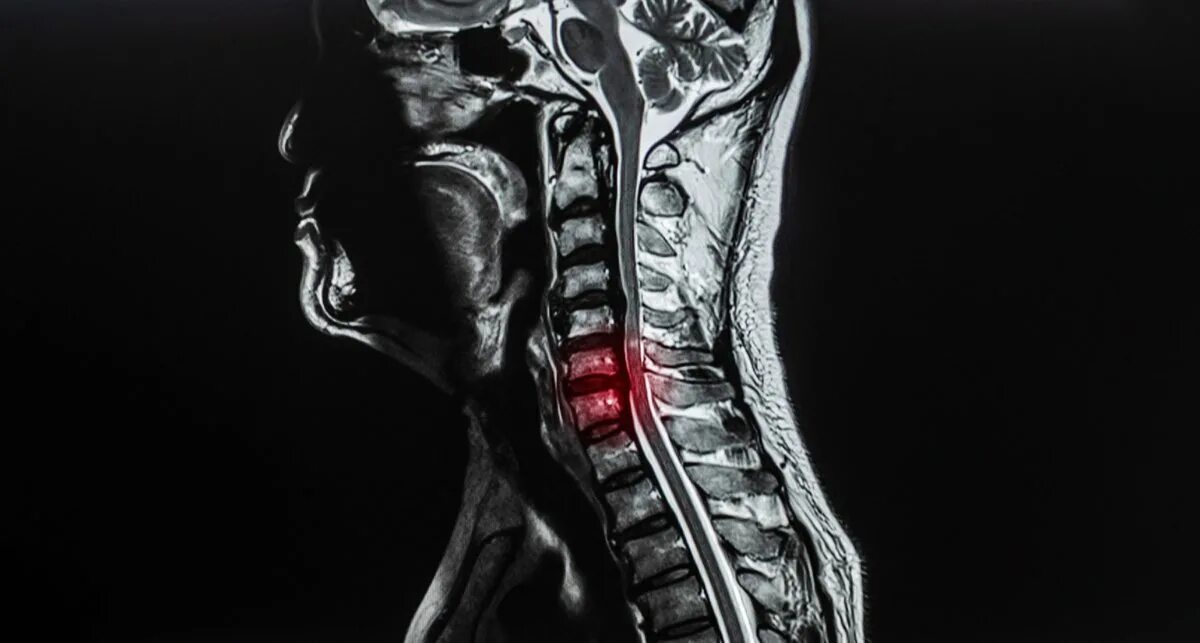

В шейном отделе мрт